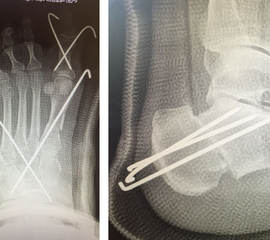

DMMO/DMDO (Distale Minimalinvasive Metatarsale Osteotomie/Distale Minimalinvasive Diaphysäre Osteotomie)

Die Indikation für eine DMMO oder DMDO (Distale Minimalinvasive Metatarsale Osteotomie/Distale Minimalinvasive Diaphysäre Osteotomie) beim Kind mit wachsendem Skelett ist nicht die klassische Metatarsalgie des Erwachsenen. In der Kinderorthopädie kann eine gute Indikation für die DMMO oder für eine DMDO der Ballen-Hohl-Fuß mit Metatarsalgie sein. Wird z. B. bei einer frühen Hohlfußkorrektur das Metatarsale I für eine bessere Rückfußeinstellung extendiert und zur Aufhebung der Extensorensubstitution die Sehne des M. tibialis posterior transferiert, kann sich im Verlauf eine Dysbalance der Metatarsalia entwickeln und eine Metatarsalgie unter II-IV auftreten. Mit einer DMDO werden die Köpfchen II-IV effektiv angehoben und die Beschwerden gebessert (Abb. 17 und 18).

Abb. 18 a-b: Beispiel einer DMDO beim Hohlfuß d.p. (dorso-plantare) Ansicht (a) und schräge Ansicht (b).

Die Indikation für eine inkomplette DMMO von dorsal Richtung plantar ist der Morbus Köhler II. Hier erfolgt eine dorsal extendierende retrokapitale Osteotomie mit verbleibender plantarer Kortikalis. Ein 1.4 oder 1.6 mm Kirschner-Draht wird in den Schaft von plantar eingeführt und das Köpfchen anschließend über einen Draht in eine verbesserte Gelenkkongruenz gedrückt und darüber gleichzeitig fixiert (Abb. 19).

Abb. 19 a-b: präoperative Diagnostik bei M. Köhler II (a) und postoperativer Verlauf nach minimaler Osteotomie und Köpfchenanhebung mit einem Draht (b).